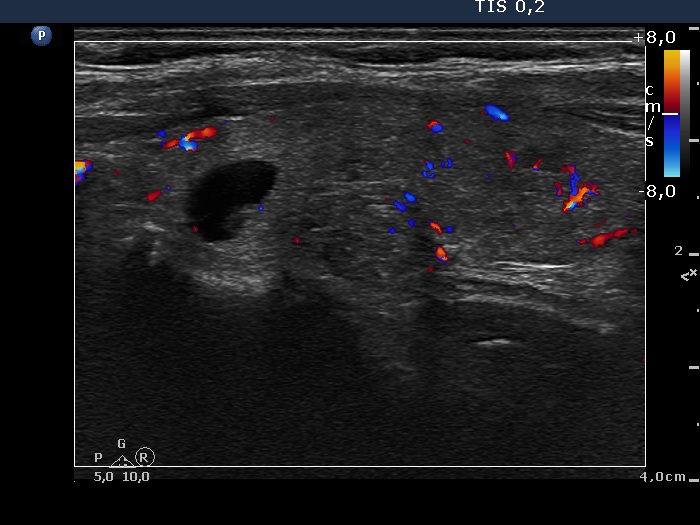

Right lobe, longitudinal scan

Left lobe, transverse scan, color Doppler mode. The vascularization is a bit increased.